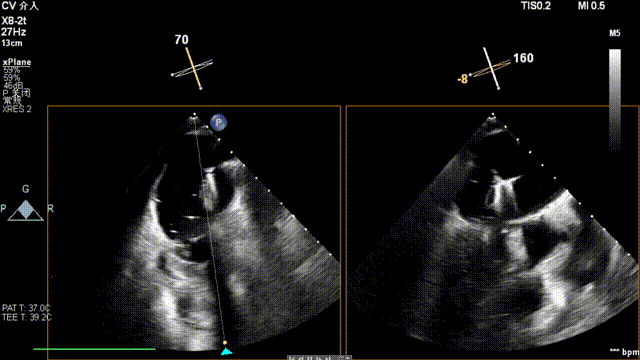

术前超声

患者为原发性二尖瓣反流(DMR),收缩期可见二尖瓣反流信号,反流位于 2 偏 3 区,基线期二尖瓣反流程度4+。

前叶长度 15.7mm,后叶长度 12.7mm,后叶脱垂宽度13.9mm,脱垂高度4.76mm, 瓣环直径37.1mm,VC:4*7mm, MVA约4cm² 。瓣叶质地较差,腱索断裂、后瓣叶脱垂。